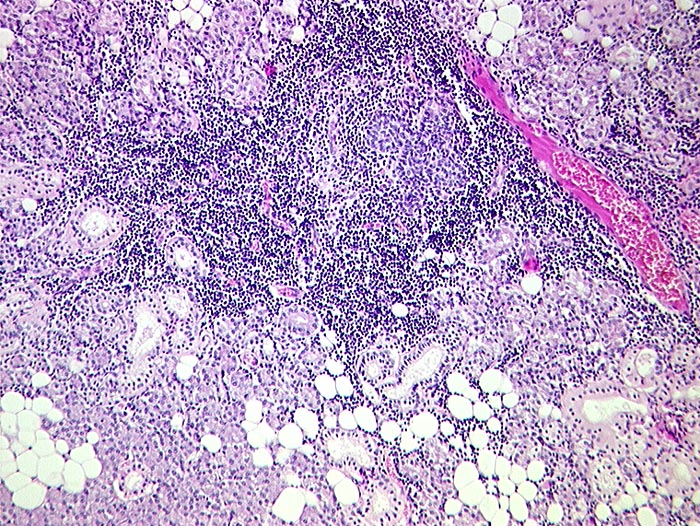

PathoPic ID 119 - Sjögren Syndrom, Parotis

Sjögren Syndrom, Parotis

Entzündung / Reparatur

Parotis

Kopf & Hals, Sinnesorgane

Sjögren Syndrom: St.n. Enukleation des linken Auges wegen spontaner Ruptur. St.n. Hornhautulzera.

Histologie

79